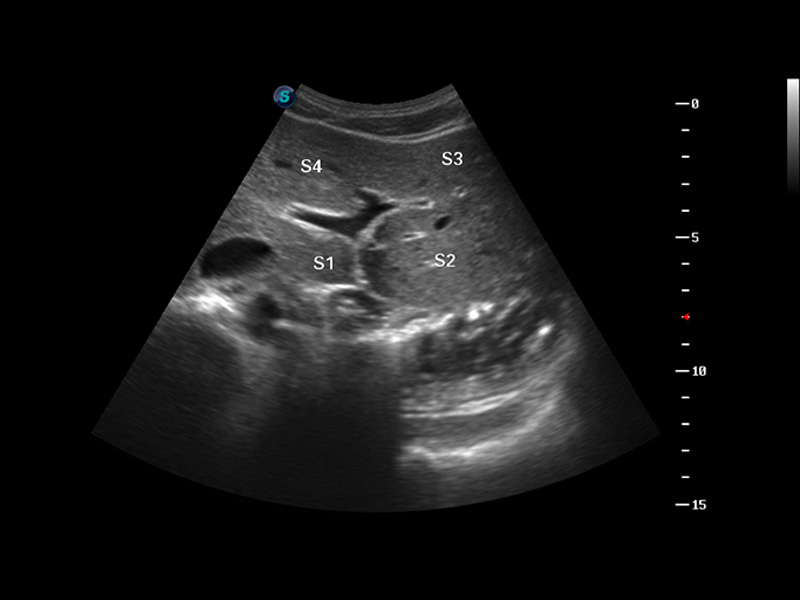

S8 EXP便携式彩色多普勒超声诊断仪是百老汇电子游戏官网研发的高端全身应用型便携彩超。高通道的VIS平台融合可视化(Visual)、智能化(Intelligent)和人性化(Smart)的特点,配以百老汇电子游戏官网自主研发生产的探头大家族,使您能够快速、准确的获得病人信息,提高工作效率的同时减轻疲劳。

多波束形成器

μ-Scan微米成像

谐波成像

实时宽景成像

空间复合成像

3D/4D成像